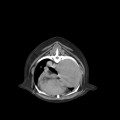

CT - lebka